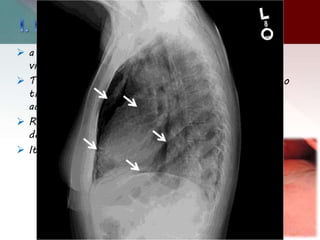

B) Bronchiectasis:

 Bronchiectasis, or the dilatation and distortion of bronchi and

bronchioles, may be mistaken for cystic airspace disease .

 Bronchiectasis may be the result of either a chronic suppurative

process or accompany lung fibrosis, when it is then referred to

as traction bronchiectasis.

 Cystic bronchiectasis can be differentiated from true cystic lung

disease by the continuous relationship of the cystic structure to

bronchial tree

 Approximately uniform, medium-sized cavities are typical of

cystic bronchiectasis.

 Valsalva and Mueller maneuvers produce rapid change in the size

of cysts, which freely communicate with the airways; this change

distinguishes cystic bronchiectasis from other conditions.